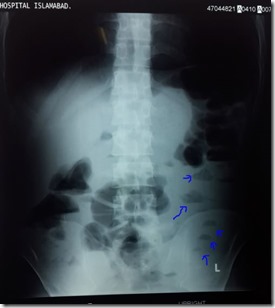

This X-Ray erect abdomen shows dilated loops of intestine along with air fluid levels. The air-fluid levels are highlighted with the help of arrows.

Following is an X-ray that is seen in case obstruction.This X-Ray erect abdomen shows dilated loops of intestine along with air fluid levels. The air-fluid levels are highlighted with the help of arrows.